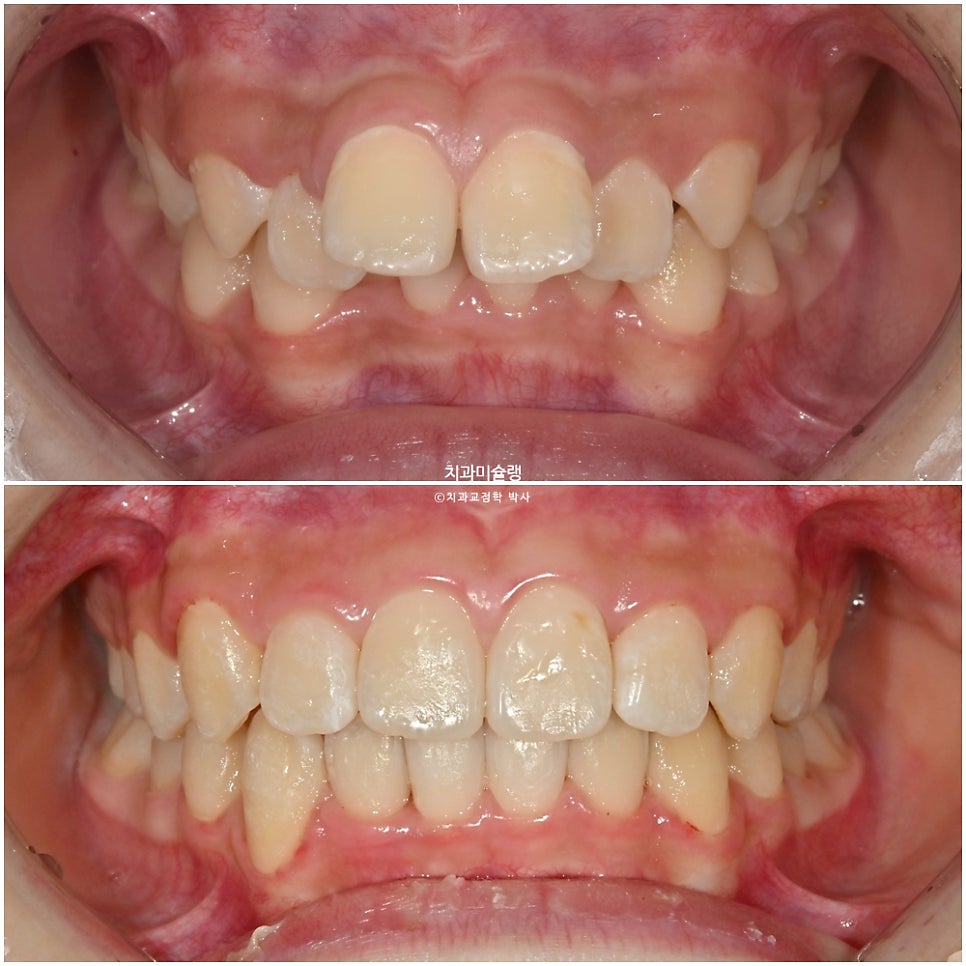

2023년 7월,

앞니 돌출과 삐뚤한 치아 때문에

교정치료를 위해 온 어린이 입니다.

아래앞니가 윗니에 가려 안보일 정도의 심한 과개교합입니다.

앞니가 튀어나온 돌출입니다.

좌우 교합관계가 모두 2급이며 특히 좌측이 더 심합니다.

아랫니도 삐뚤삐뚤 합니다.

유치가 남아있고 나이가 11세 미만이라 인비절라인퍼스트 어린이교정이 가능한 상황 입니다.

이제 전후비교 보겠습니다.

2023.07-2025.12

과개교합, 중심선의 개선.

앞니 돌출의 개선

2급 교합관계가 1급 교합관계로 개선되었습니다.

앞니 돌출이 개선되며 미소가 예뻐졌습니다.